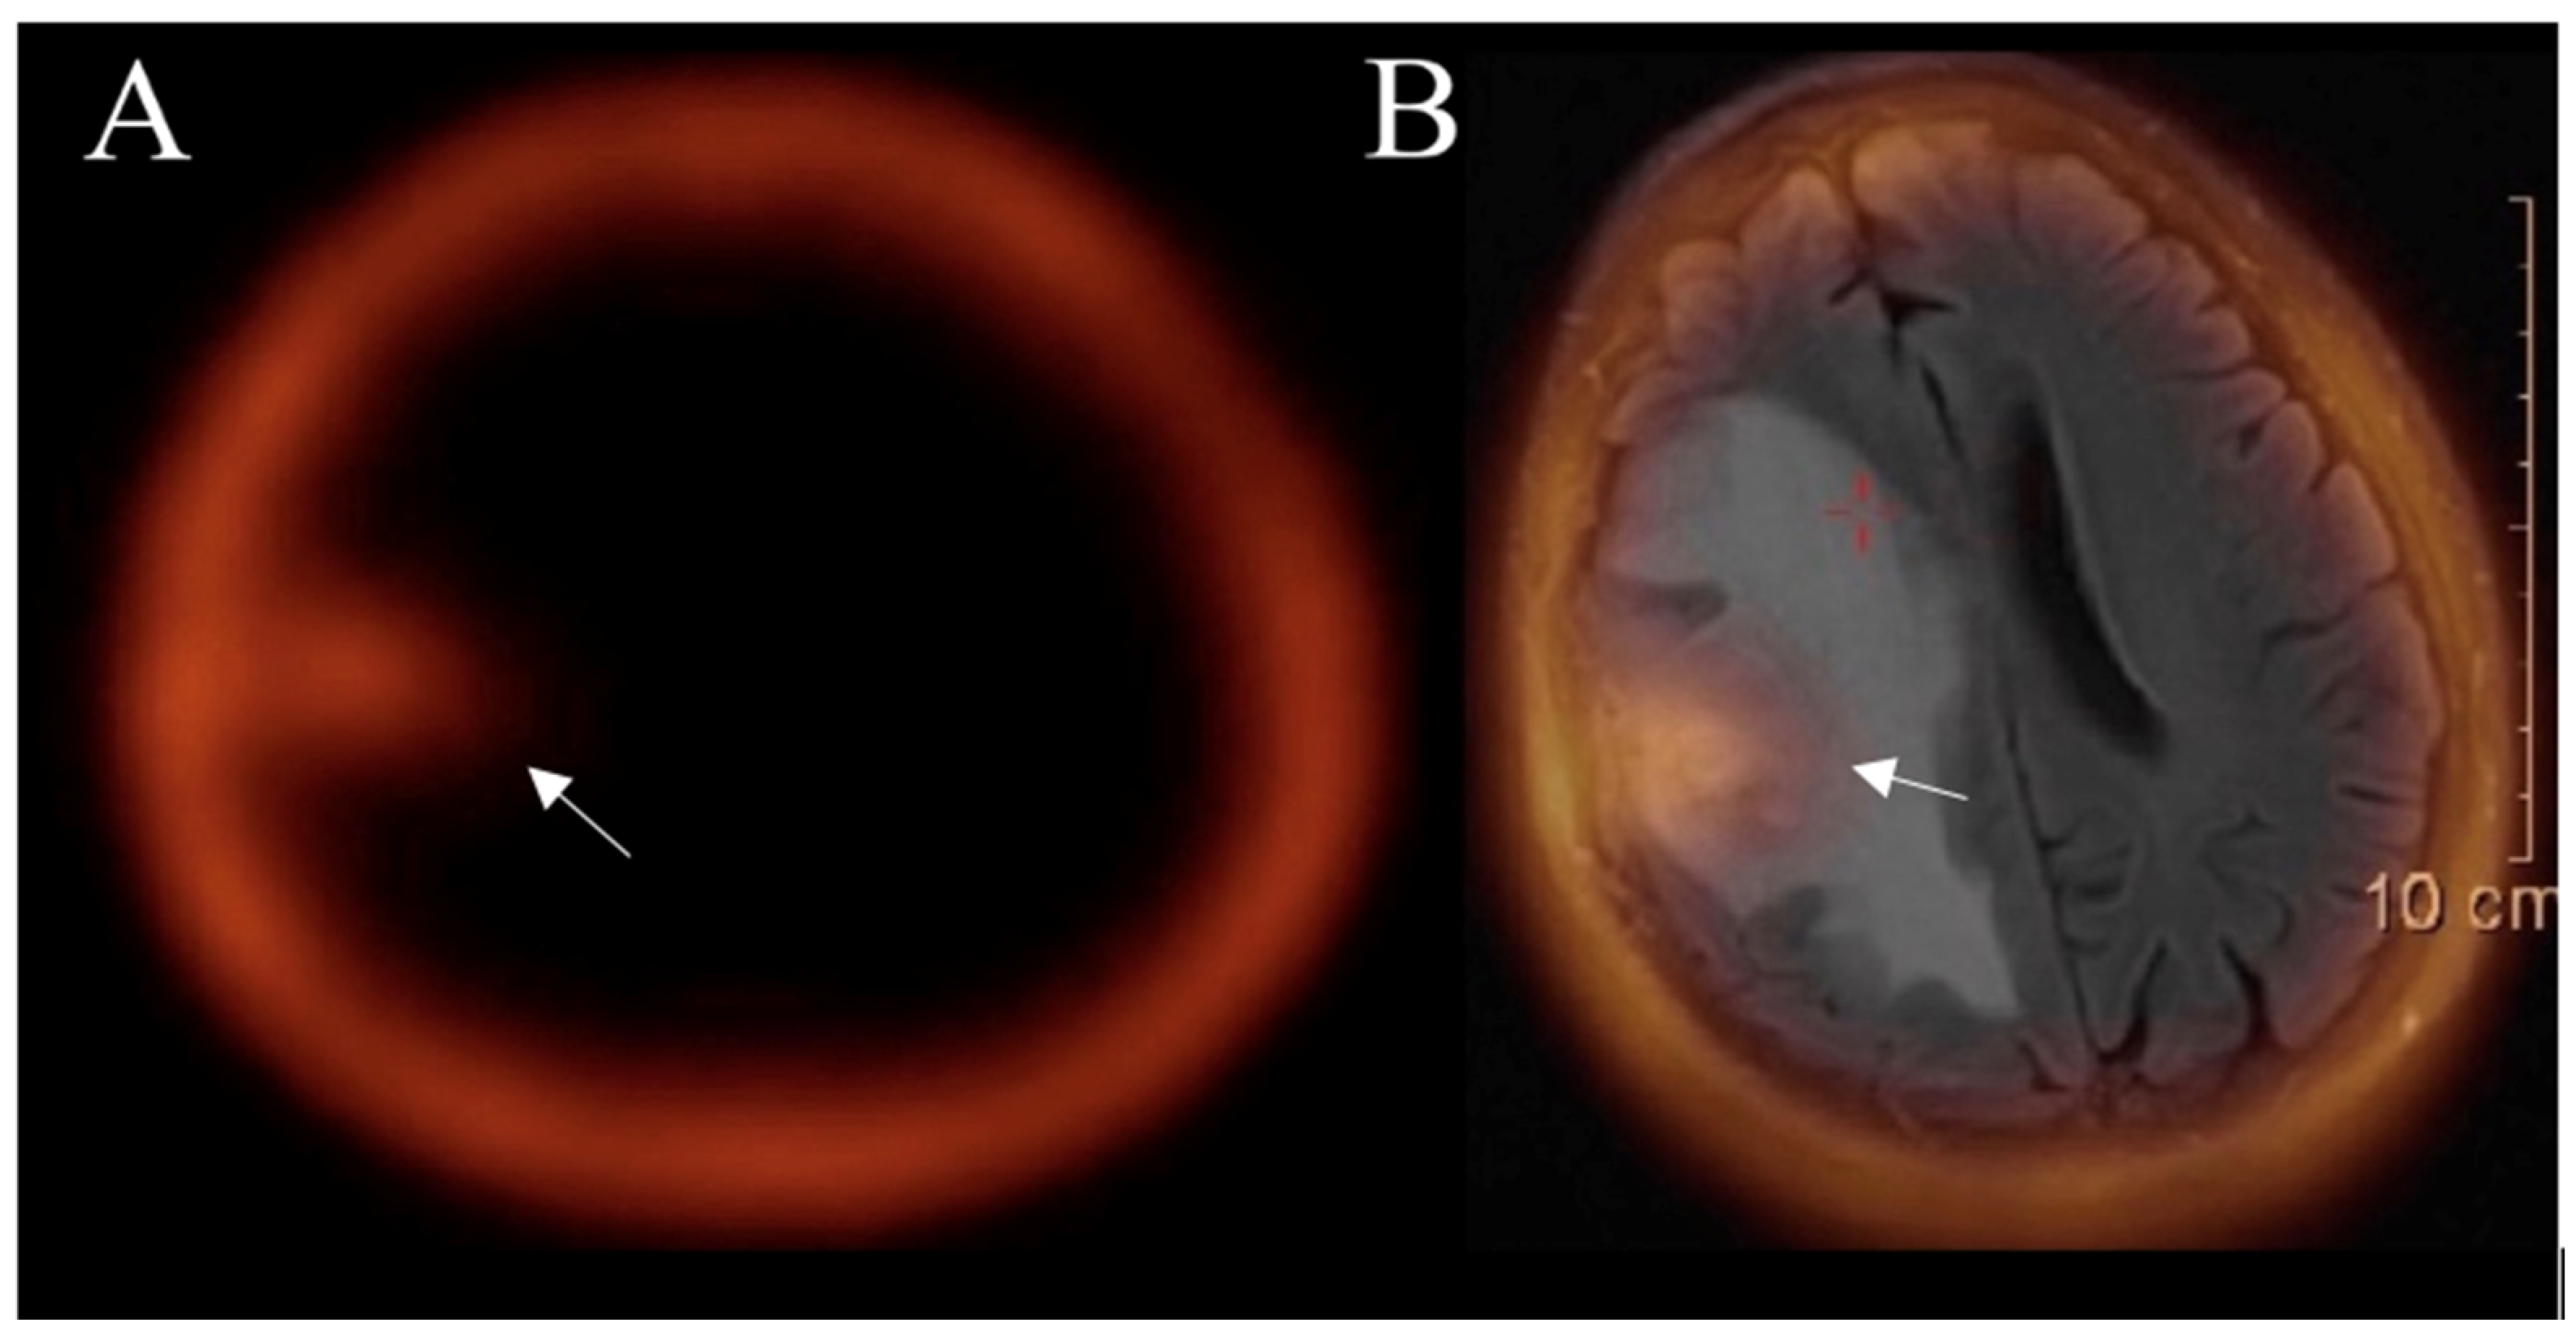

3.5.1. Positron Emission Tomography

3.5.2. SPECT